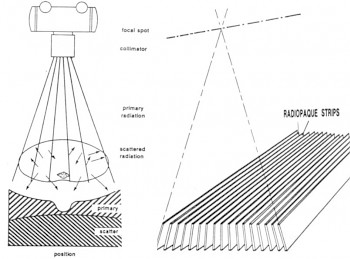

Ein Streustrahlenraster ist eine Vorrichtung in der Röntgentechnik, die vor dem Bildempfänger (Bildschirm, Detektor oder Film) angebracht ist und den Einfall von Streustrahlung auf diesem reduziert. Dadurch wird der Kontrast des Röntgenbildes erhöht.

Streustrahlen entstehen überwiegend durch Streuung der Röntgenstrahlen im durchleuchteten Objekt. Die das Bild erzeugende Strahlung ist direkt von der Röntgenröhre auf den Bildträger gerichtet, die Streustrahlung hat jedoch davon abweichende Richtungen. Streustrahlung verursacht eine relativ gleichmäßige Dosisverteilung am Detektor. Der relative Anteil der Streustrahlung steigt stark mit zunehmender Objektdicke und nimmt ab mit höherer Energie der Röntgenstrahlung d. h. steigender Röntgenröhrenspannung.

Die im Patienten erzeugte Streustrahlung führt zu kontrastarmen, verrauschten Bildern, die ohne Zusatzmaßnahmen diagnostisch nicht auswertbar sind. Sie trägt zwar zur Filmschwärzung mit bei, ist aber weitgehend unerwünscht, da sie wie ein Schleier über dem Primärstrahlenbild liegt.

Das Raster ist wie eine Lamellenjalousie aus schmalen Streifen von stark absorbierendem Material (meist Bleifolie) und durchlässigeren Abstandhaltern (meist Spacern aus Aluminium oder Zellulose) aufgebaut.

Die Streifen stehen parallel zur Strahlung. Die erwünschte gerichtete Strahlung kann die Spacerstreifen durchdringen, Streustrahlung bleibt in den Bleistreifen hängen.

Durch das Streustrahlenraster gelangen im Wesentlichen nur die genau in Längsachse der Rasterschächte und somit direkt vom Fokus ankommenden Quanten. Alle anderen werden weitgehend von den Bleilamellen absorbiert.